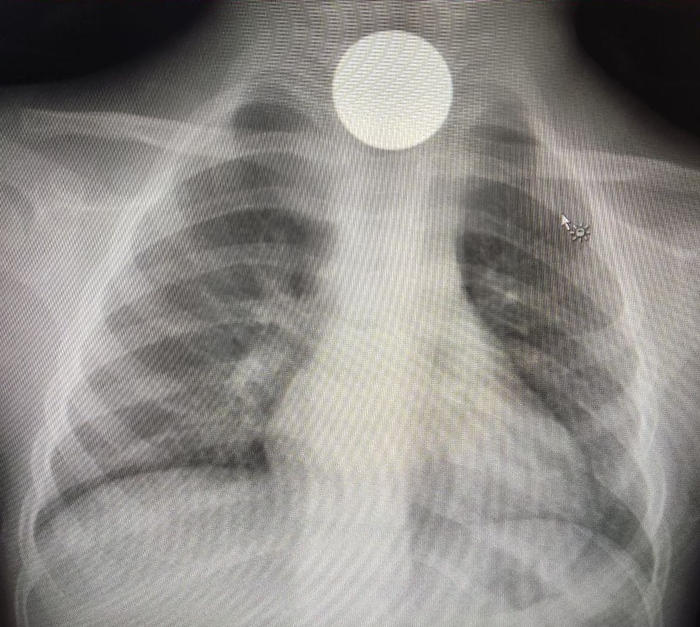

Снимок брюшной полости оказался в полном порядке. Для ребёнка, который за неделю ел всего 1 раз накануне заболевания и то банан, в целом очень даже хорошо. Пришла пора и снимка грудной клетки. Со снимка на меня смотрел яркий, идеальный круг. А я на него.

Дело в том, что разные предметы и ткани по разному поглощают либо пропускают рентгеновские лучи. Кости, металлические предметы хорошо их поглощают и выглядят на снимке белыми, хотя юмористы рентгенологи называют это затемнением. А ткани, которые хорошо пропускают лучи остаются тёмными.

Соответственно наш круглый предмет должен быть чём-то плотным. Костью? У человека нет такой кости. Значит, остаётся один вариант - инородное тело.

Дальше остаётся дело за малым. Произведён второй просмотр снимка совместно с рентгенологами. Пневмонии как не было, так и нет. Но описано инородное тело пищевода.

Дальше маленького пациента ожидали в отделении эндоскопии, где из него извлекли пятерублевую монету. Наверное там же с ним и была проведена беседа о том, что инвестировать в себя надо иначе.